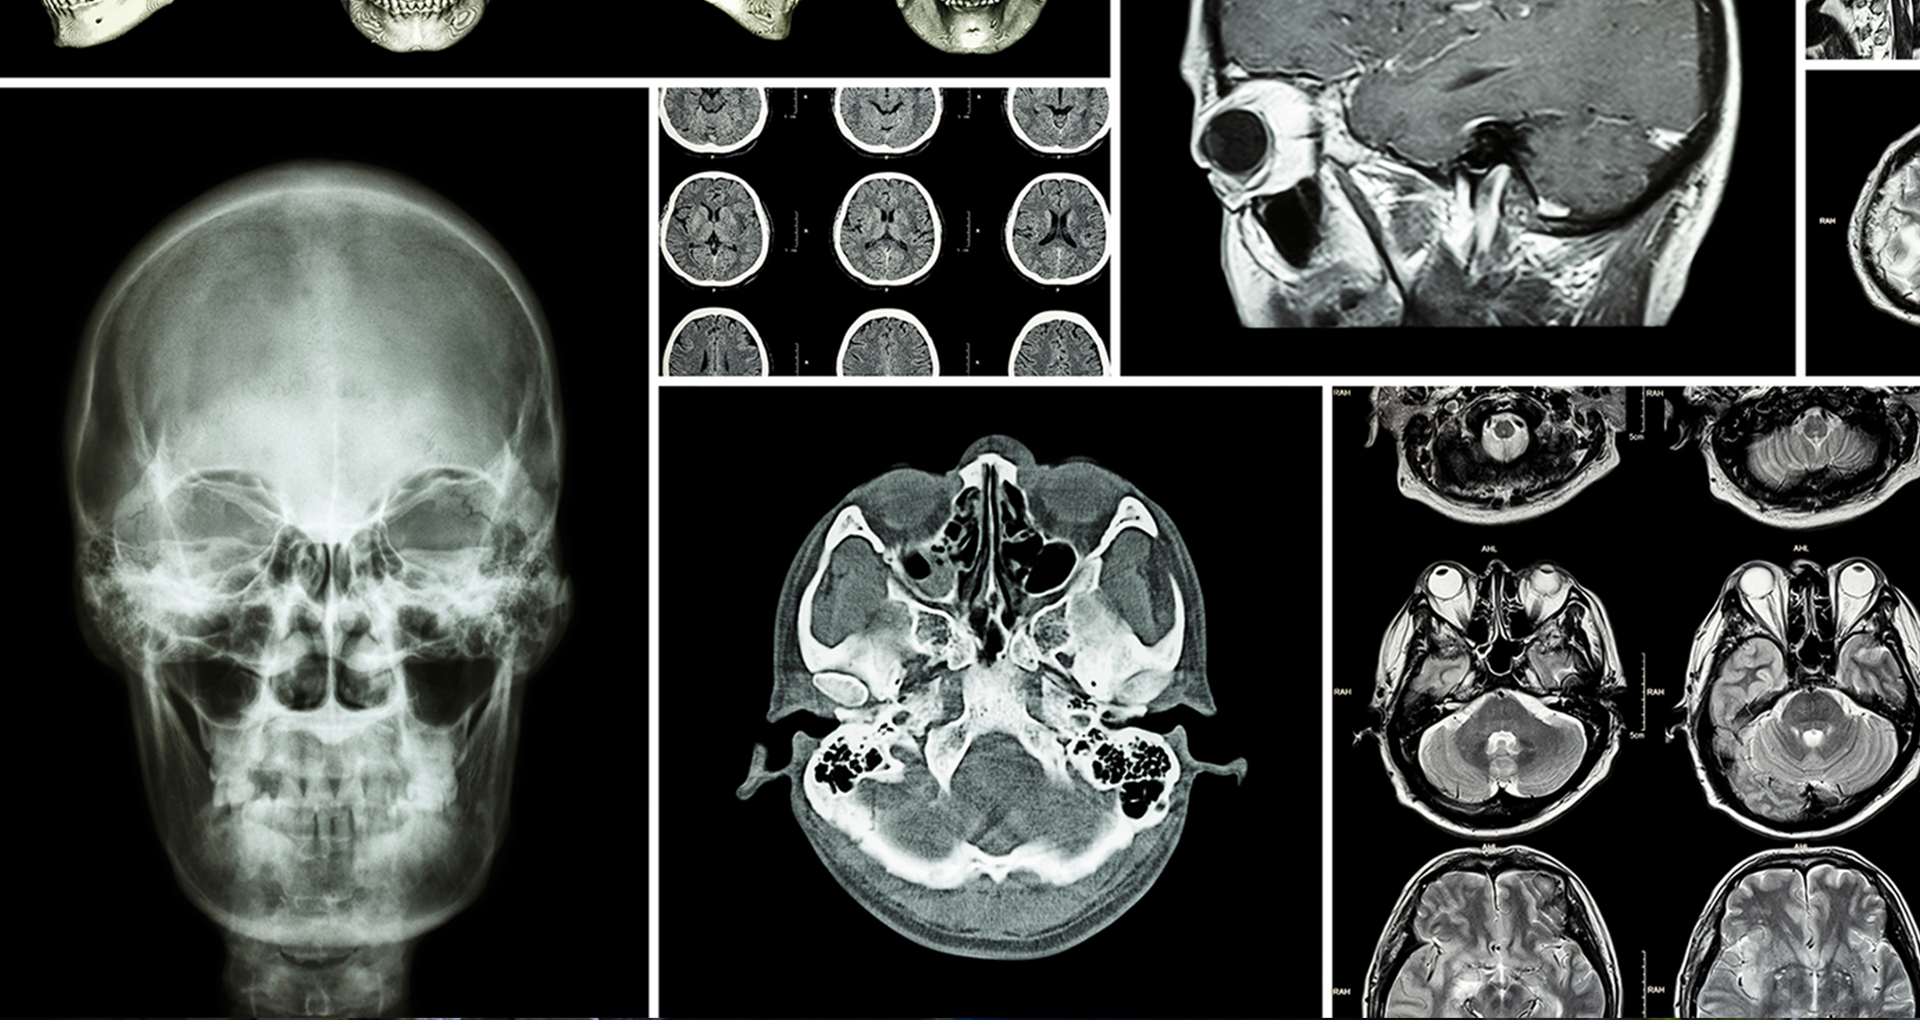

This degree covers a range of physical science topics with applications in medicine, such as radiotherapy and imaging.

The technical aspects of medical physics will be covered in subjects concerning medical imaging, radiotherapy, and radiation transport modelling.